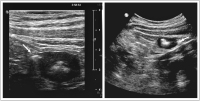

Kolon-Divertikulitis: Diagnostik und sonographisch gesteuerte Therapie

Journal für Gastroenterologische und Hepatologische Erkrankungen 2009; 7 (2): 13-18 Volltext (PDF) Summary Praxisrelevanz Fragen zum Artikel Abbildungen